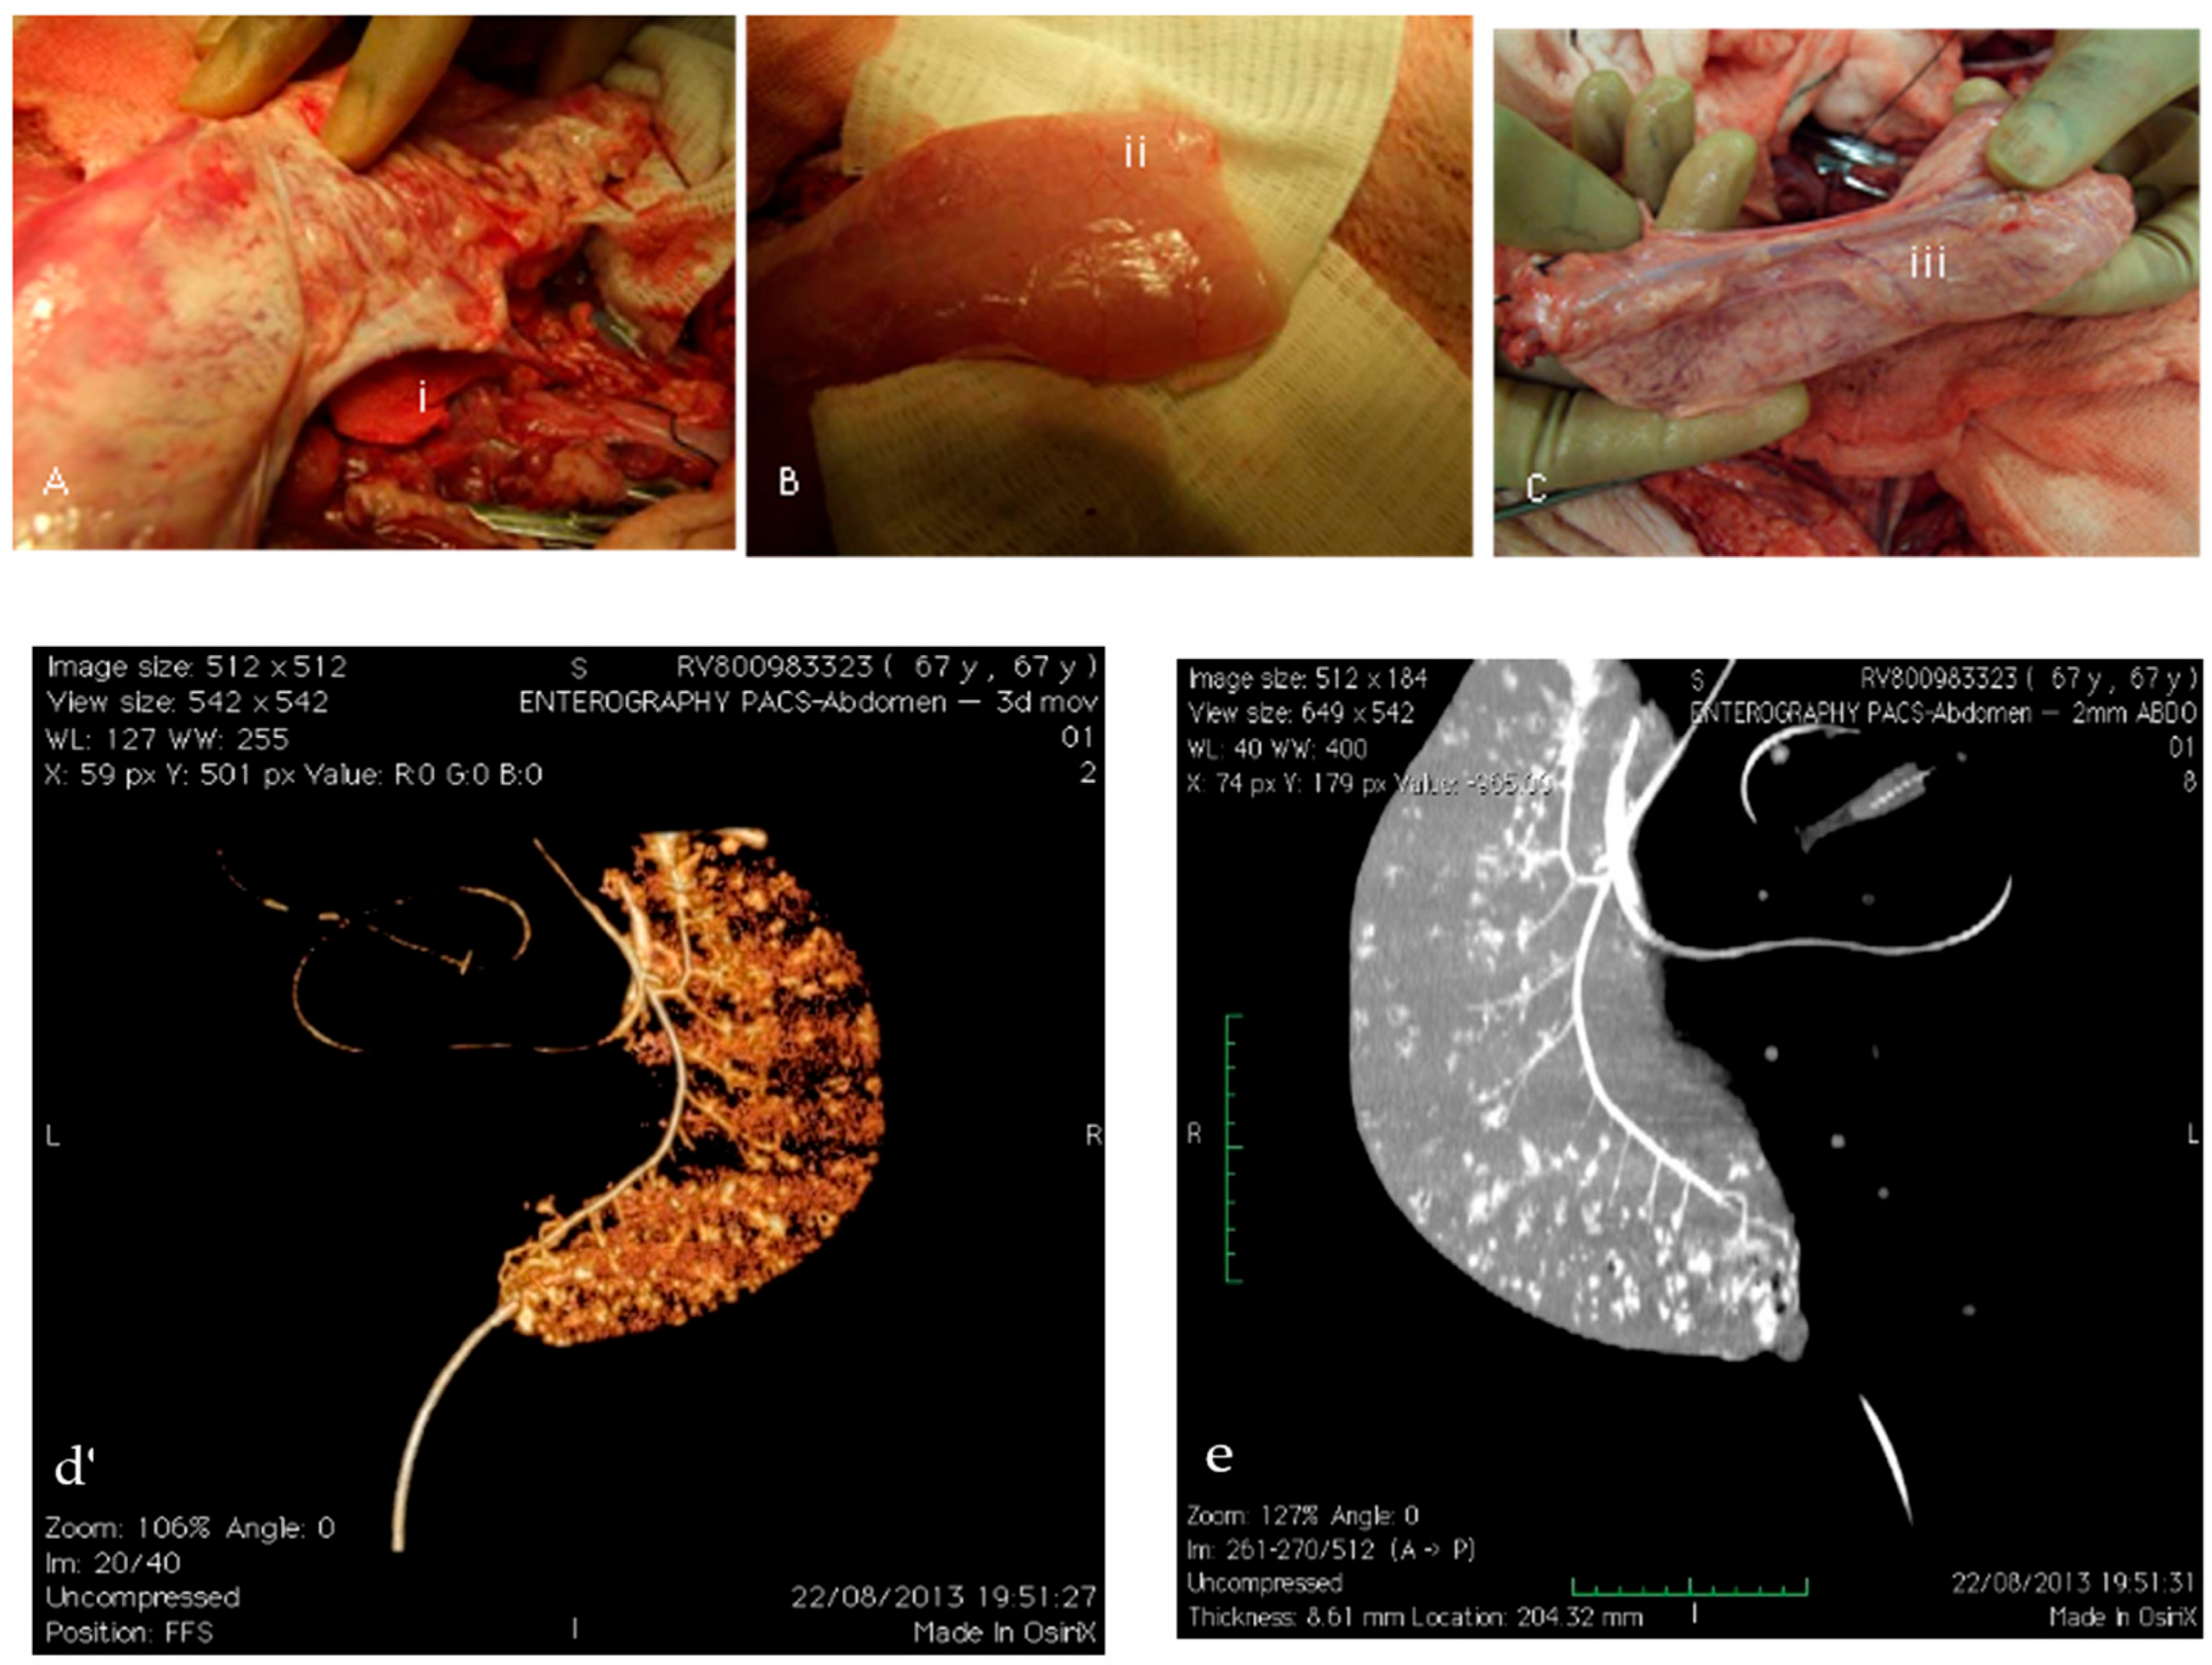

3.4. Vascular Transplantation and CT Angiographic Evaluation

3.5. Perfusion Studies and Vascular Integrity